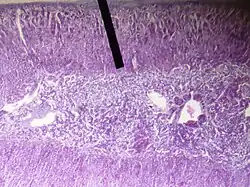

The zona reticularis (sometimes, reticulate zone) is the innermost layer of the adrenal cortex, lying deep to the zona fasciculata and superficial to the adrenal medulla. The cells are arranged cords that project in different directions giving a net-like appearance (L. reticulum - net).[1]

Adrenal gland (zona reticularis layer).